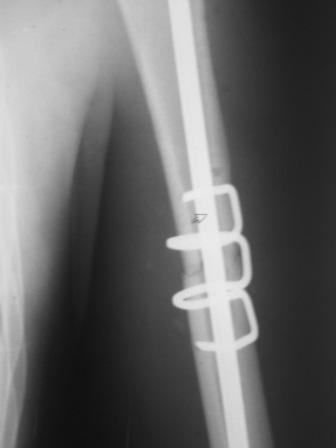

Re: Перелом н\3 плечевой кости. Тактика лечения?

Да, как раз блокированная пластина и стоит, не синтезовская метадиафизарная, Рыбинская, но на порядок дешевле, а профилактика всех осложнений - в данном конкретном случае, начало ранней на вторые сутки - после удаления дренажа разработки движений в смежных суставах. Если же идти с ревизией т.е. всё равно, открыто как вариант небольших разрезов при поперечном переломе можно и комбинированный мос (см.на вкладыше), хотя думаю для такого способа перелом всётаки низковат.